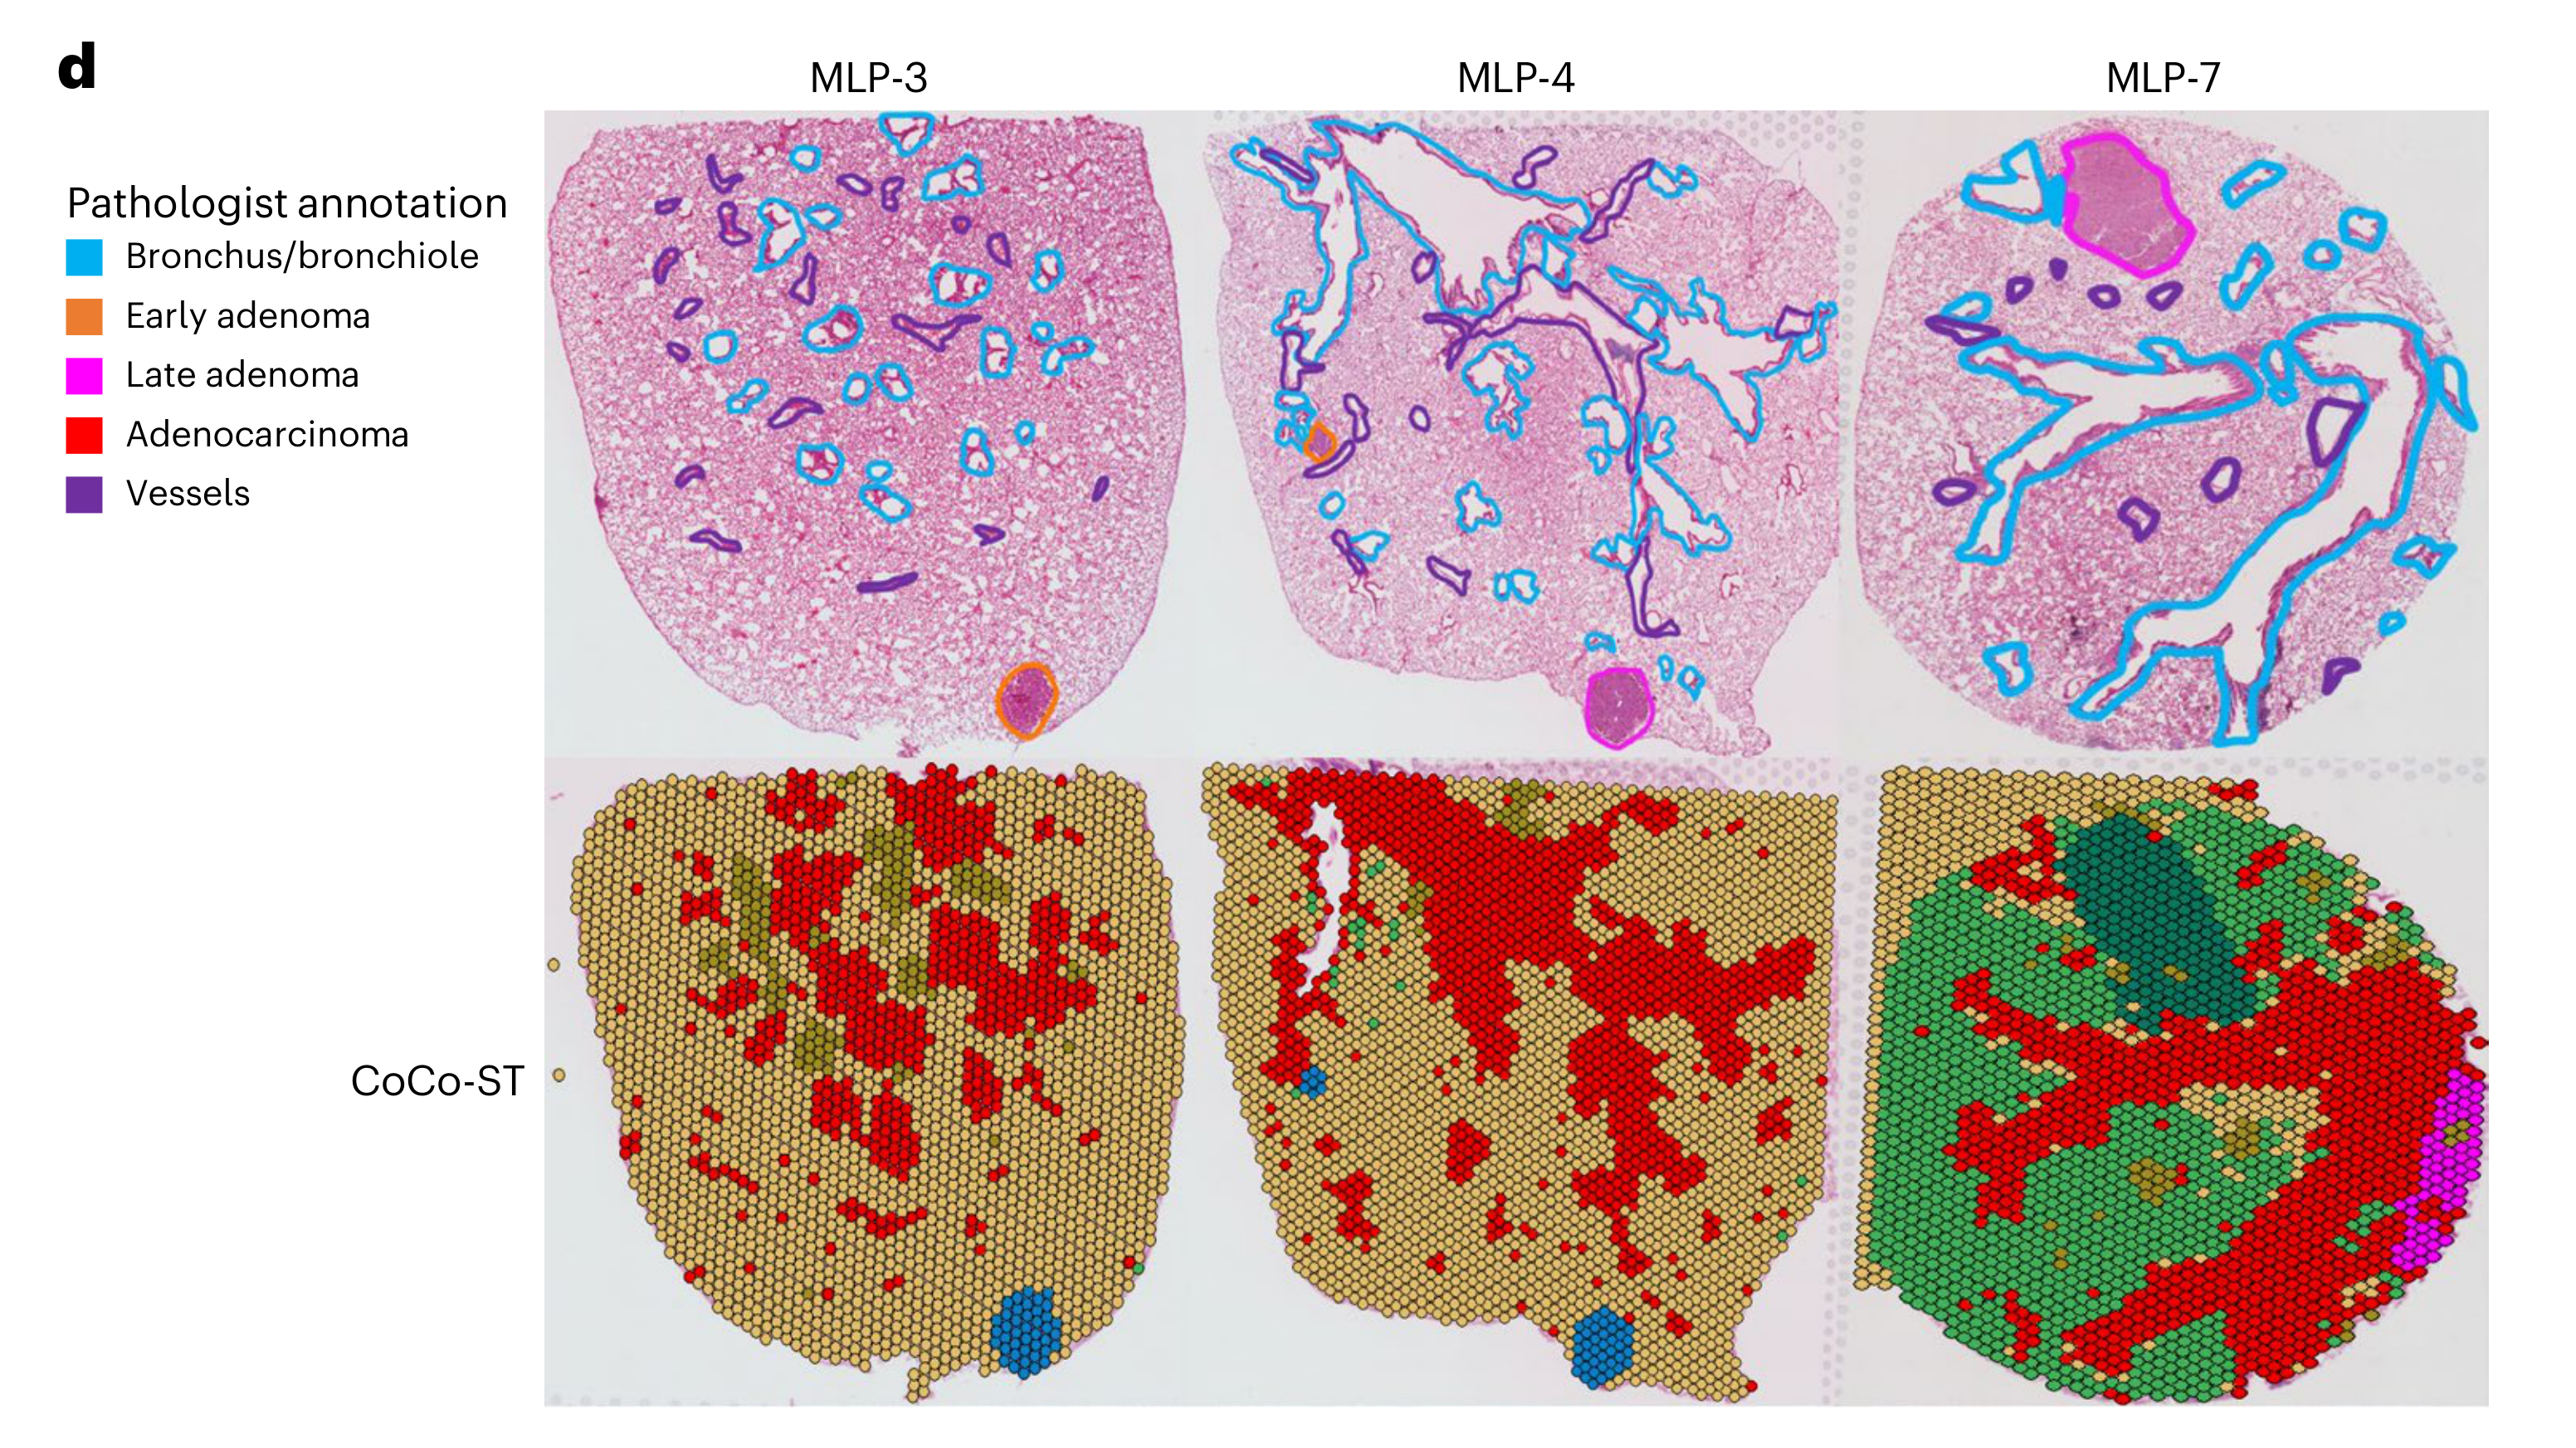

What is the spatial distribution of disease subtypes?